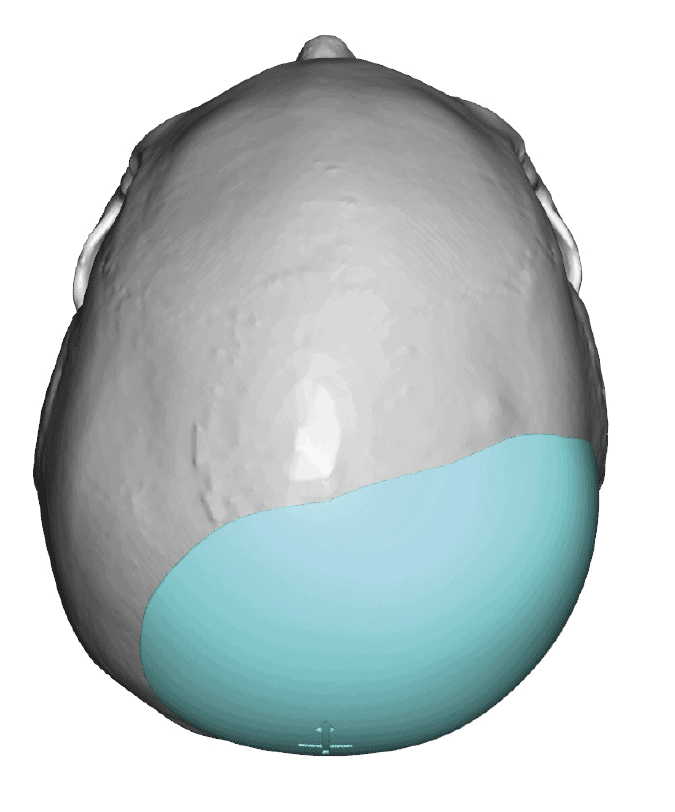

Desire for rounder shape to the top of the head from a congenital parasagittal deficiency skull shape.

Custom skull implant designed to fill in the parasagittal deficiencies.

Desire for rounder shape to the top of the head from a congenital parasagittal deficiency skull shape.

Custom skull implant designed to fill in the parasagittal deficiencies.